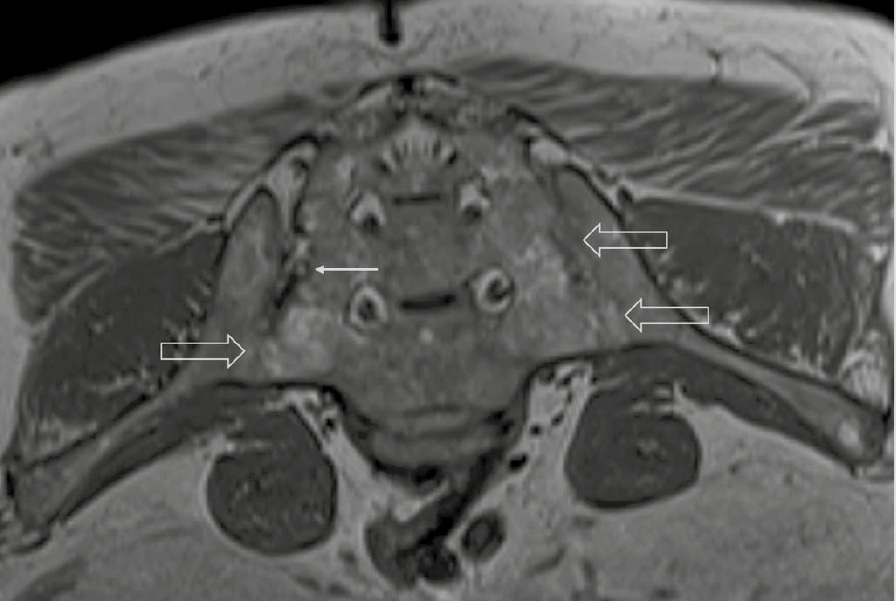

При компьютерной томографии органов грудной клетки данных за «свежие» очаговые и инфильтративные изменения не получено. Увеличения лимфатических узлов подмышечных областей, средостения, корней легких не выявлено. Отмечался усиленный грудной кифоз, обызвествление передней продольной связки, на всем уровне исследования определялись передне-боковые спондилофиты, а также анкилоз большинства реберно-поперечных суставов. По данным рентгенографии кистей (рис. 1, 2) и стоп (рис. 3, 4) диагностированы признаки эрозивного артрита, анкилоз суставов запястья. По данным МРТ крестцово-подвздошных суставов (КПС) определялся неравномерный анкилоз КПС, хрящи по суставным поверхностям неравномерной толщины, примерно на половине протяжении сустава отсутствуют, «суставной промежуток» облитерирован. Неравномерность и нечеткость контура суставных поверхностей за счет множества краевых эрозий справа, единичных – слева, с наличием остеокластоза, в нижнем отделе слева по смежным отделам определяются участки трабекулярного отека, данная находка клинически интерпретирована как двусторонний активный сакроилиит (рис. 5, 6).

Рис. 6. Магнитно-резонансная томография (Т1-взвешенное изображение в косой корональной проекции). Протяженные участки анкилоза крестцово-подвздошных суставов (толстые стрелки), субхондральная киста правой латеральной массы крестца (тонкая стрелка). При магнитно-резонансной томографии крестцово-подвздошных сочленений с обеих сторон определяются крупные зоны анкилоза (суставные щели полностью облитерированы на 1/3 поверхности сустава справа, на 2/3 поверхности слева, что соответствует III рентгенологической стадии сакроилиита справа, IV стадии слева по Келлгрену). На остальных участках суставной хрящ неравномерно истончен, суставные поверхности неровные за счет множественных эрозий справа, единичных – слева. Определяются единичные мелкие (4 мм) субхондральные кисты справа